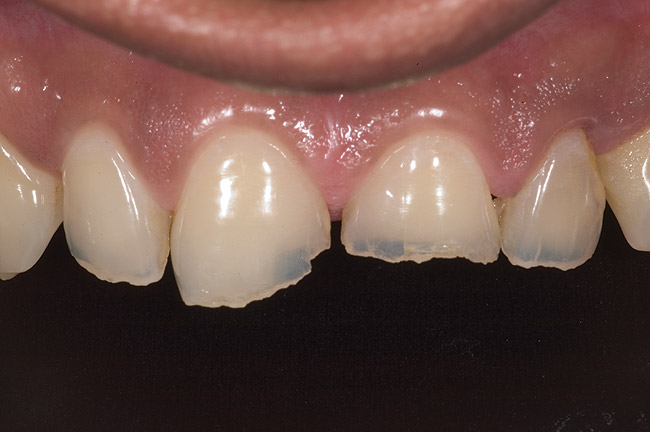

Figure 6  1:1 view demonstrating severe loss of tooth structure due to palatal erosion.

Figure 6

Examination revealed that palatal surfaces of teeth Nos. 6 through 11 showed severe loss of tooth structure, with mild wear on the lower incisors and loss of anterior guidance (Figure 5 through Figure 7). The palatal TSL was consistent with the clinical picture presented by patients with gastric reflux. A detailed medical history was taken, and the patient complained of having heartburn and acidity at least 4 out of 7 days a week. He had never sought treatment for it and used over-the-counter medication when needed. He was a nonsmoker, with occasional intake of alcohol. He had a high-stress job with irregular meal times. A thorough smile and dental analysis11 was carried out; the findings appear in Table 2.